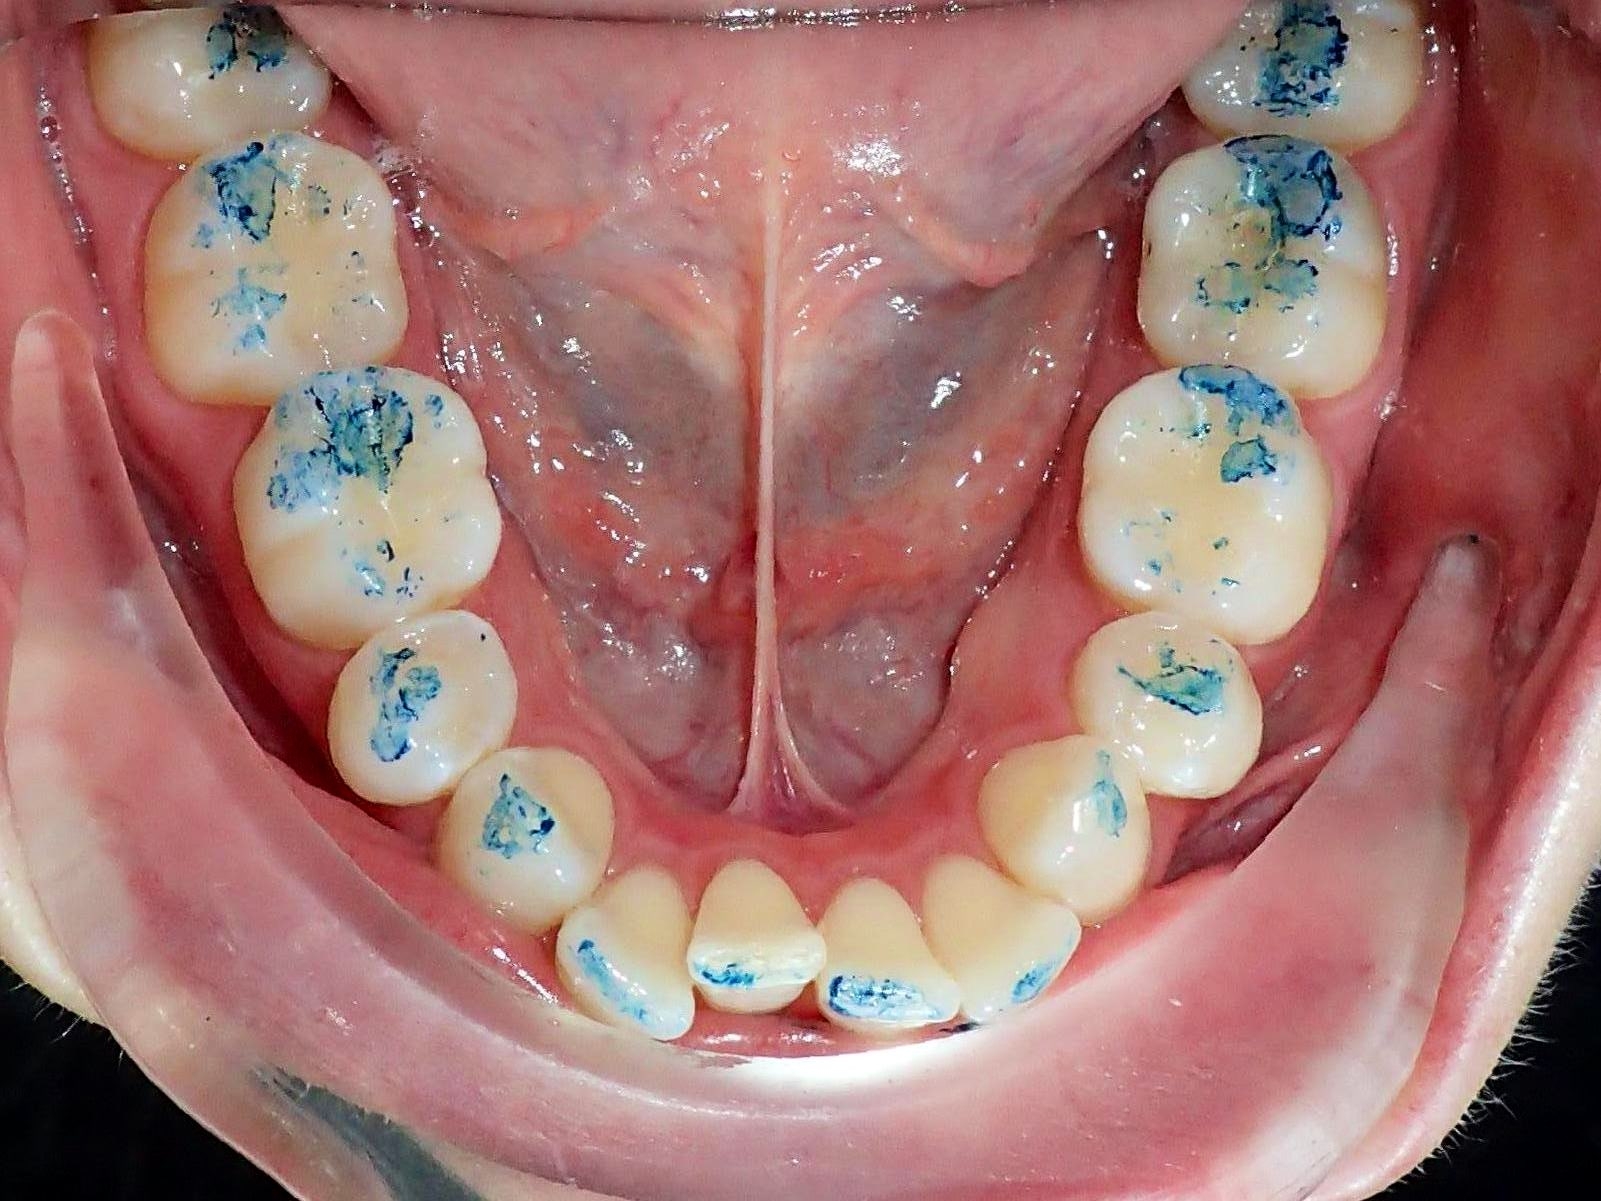

До / После

Лечение Invisalign в течение 9 месяцев при сильной скученности